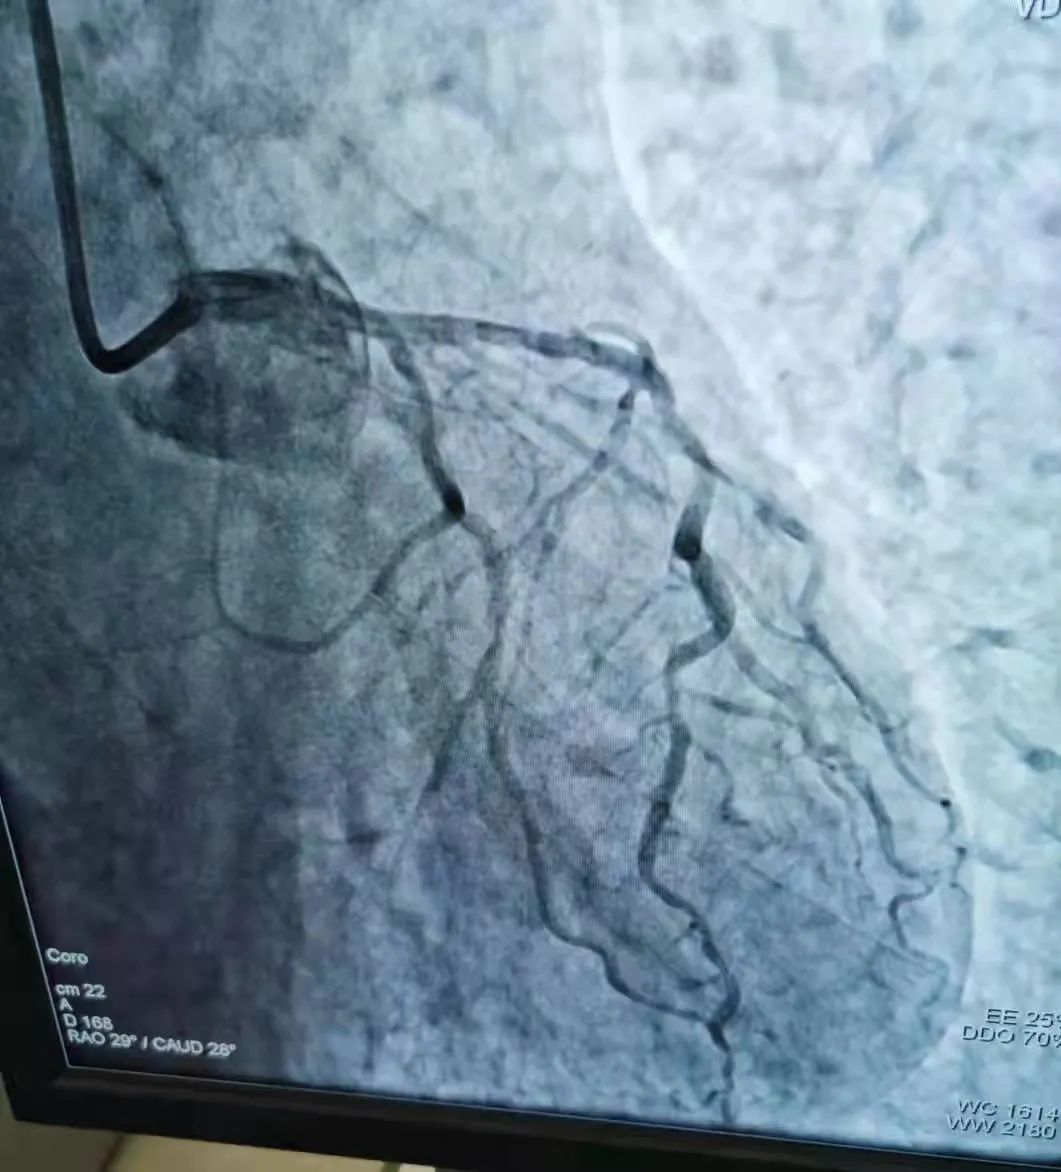

近日商城县人民医院心血管内科介入团队与"死神"赛跑,争分夺秒施术,成功救回一名77名急性心肌梗塞老人,这是我院独立、成功开展的第50例急诊PCI手术,是我院心脏介入技术发展过程中一个重要里程碑,标志着我院在急性心肌梗塞的诊疗技术日臻成熟,也显示出我院在介入治疗领域已具备较强的综合实力。 学科联动,无缝衔接,及时高效 2021年9月1日夜晚9时许,商城县人民医院胸痛中心建设群里上传了一份心电图检查报告,急诊医学科值班医师发来这样一条信息:“男性患者77岁,已胸痛4小时余,请心血管内科医师会诊”。心血管内科值班医师迅速作出判断后回复“急性下壁非ST段抬高性心肌梗塞、建议完善心肌标志物检查,请即刻跟患者家属谈话,建议尽快进行急诊介入治疗。”经过与家属成功沟通后,患者由急诊绿色通道被送往介入手术室,而心血管内科介入团队此时已火速到达了手术室,与此同时,心血管内科熊晨晖主任结合患者临床症状,并仔细查看患者的急查心电图及心肌标志物的检查结果后给出指导性意见:“患者年龄大,血流差,术中密切观察患者病情变化!”随后经介入团队密切配合,快速实施冠脉造影术及冠脉治疗术,患者病情由此转危为安,胸痛症状完全消失,30分钟后,手术顺利完成。该患者术后目前恢复情况良好。 术前心电图、心肌酶谱提示下壁急性心梗 冠脉照影结果及冠脉治疗后对比 什么是急诊PCI术 急诊PCI术是指在患者发生急性心肌梗塞后12小时内进行的冠状动脉血运重建,患者首先在导管室行冠状动脉造影术,找出冠状动脉“罪犯”血管及其病变部位,对病变部位行经皮冠状动脉腔内成形术和植入支架术,使闭塞的血管得以再通,从而改善心肌的血流灌注,使梗死的相关心肌得以及早的再灌注和功能恢复。因此,可以说,急诊PCI术为挽救急性心梗垂危的生命在最短的时间内构建了一条绿色通道,提高危重症病人的抢救成功率,且术后恢复快,患者生活质量能得到很大的提高。 坚守的力量:无论身在何处,电话就是命令! 商城县人民医院心血管内科于2018年10月开始在郑州大学第一附属医院、郑州大学第二附属医院专家的指导下开展了冠脉支架植入手术,至今已有500余例,自2021年3月以来,独立开展、完成急诊PCI手术50余例,效果良好,极大的提高了此类患者的救治率,降低了死亡率和致残率。一台台成功的手术、一个个因救治及时而重获新生的患者,无不体现着我院心脏介入团队精准的诊治水平! 急诊PCI对医院的硬件、人员配备等要求极高,因此,能否开展急诊PCI目前已成为心血管领域彰显医院整体诊疗水平的标志。在短短的150天里,骄人成绩的取得与我院院党委的正确领导、多学科联动机制的灵活运用、心血管内科介入团队医护人员对职业的信仰、使命的担当息息相关。不论白昼还是黑夜、疾风或是暴雨,胸痛中心的电话就是命令!他们始终秉承:时间就是生命,时间就是心肌,与时间赛跑,与死神搏斗!以最快的速度为急性心肌梗死患者“抢时间”,随时待命为大别山区心血管疾病患者保驾护航! 就医地址: 冠心病监护病房(CCU): 2号病房楼3楼。 咨询电话: 0376—7975373; 心血管内科病区: 2号病房楼4楼。 咨询电话: 0376—7973137;